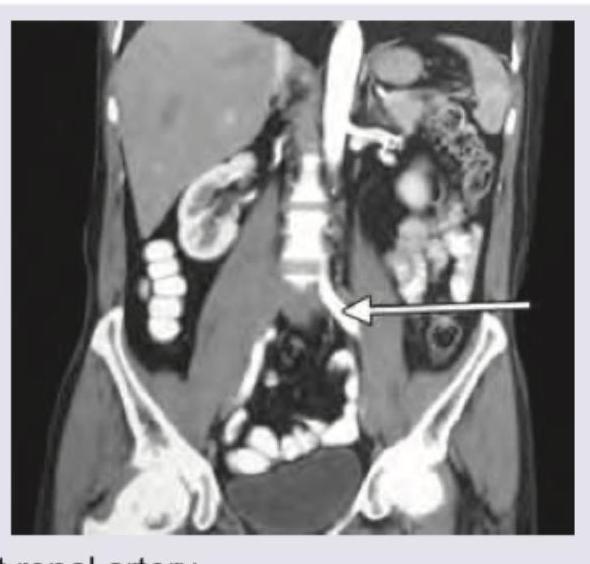

The structure shown below is:

Explanation: ***Left ureter*** - The arrow points to a tubular structure originating from the left kidney and descending towards the pelvis, which is consistent with the anatomical course of the **left ureter**. - Its relatively thin, unbranched appearance distinguishes it from major blood vessels in this region. *Left renal artery* - The **left renal artery** would originate directly from the aorta, usually superior to the structure indicated, and would be a wider, more prominent vascular structure heading towards the kidney. - Renal arteries carry oxygenated blood and appear as high-density structures on contrast-enhanced CT, but the pointed structure is too inferior and thin. *Left common iliac artery* - The **left common iliac artery** is a large artery forming from the bifurcation of the aorta, typically lower in the abdomen, near the sacrum, and would be much wider and brighter on a contrast-enhanced CT. - The indicated structure is much thinner and more superior than where the common iliac artery typically begins. *Left inferior mesenteric vein* - The **left inferior mesenteric vein** usually drains into the splenic vein or directly into the superior mesenteric vein or portal vein, located more superiorly and medially than the structure indicated. - While tubular, its anatomical course and typical size do not match the structure pinpointed by the arrow, which appears to connect to the kidney.